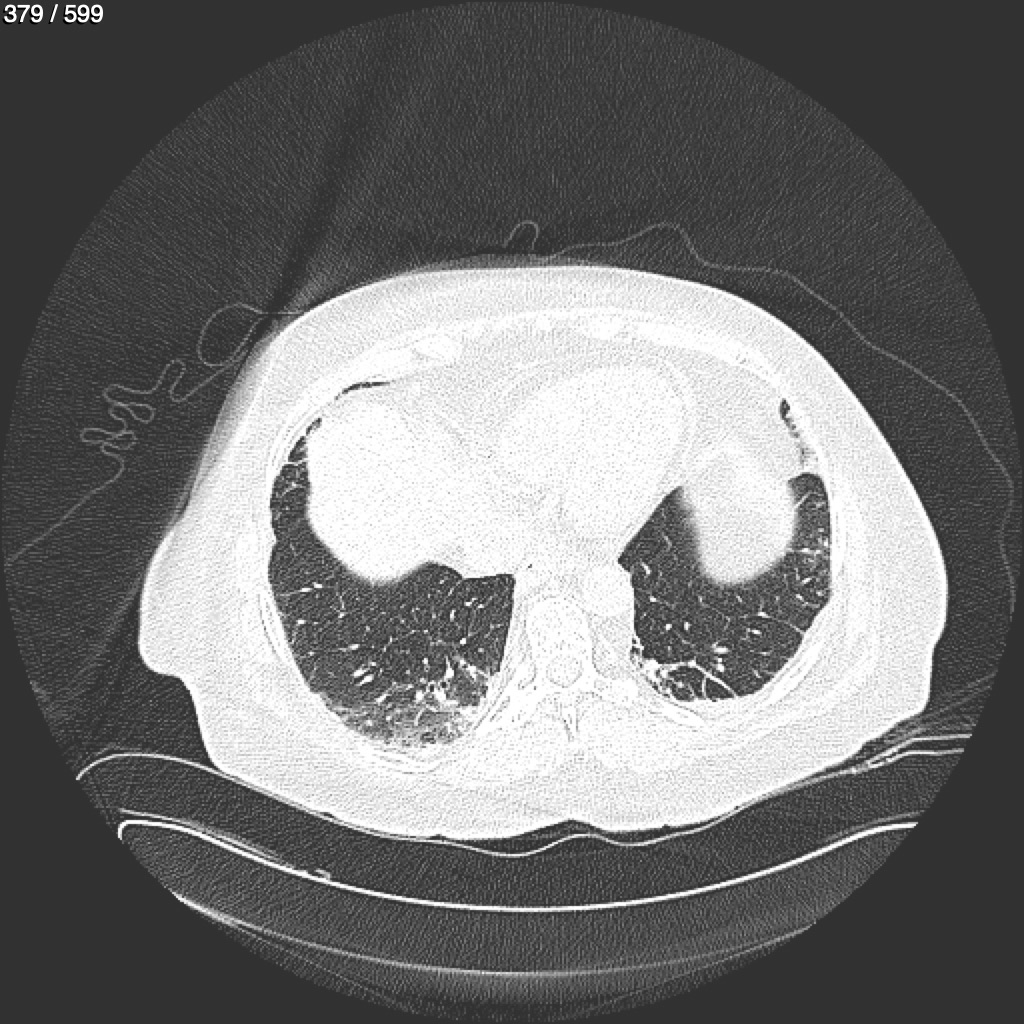

Home G​l​o​r​i​a​ ​G​l​a​d​y​s​ ​B​e​a​s​l​e​y​ ​-​ ​T​ó​r​a​x​ ​T​o​r​a​x​_​S​i​m​p​l​e​ ​(​A​d​u​l​t​o​)